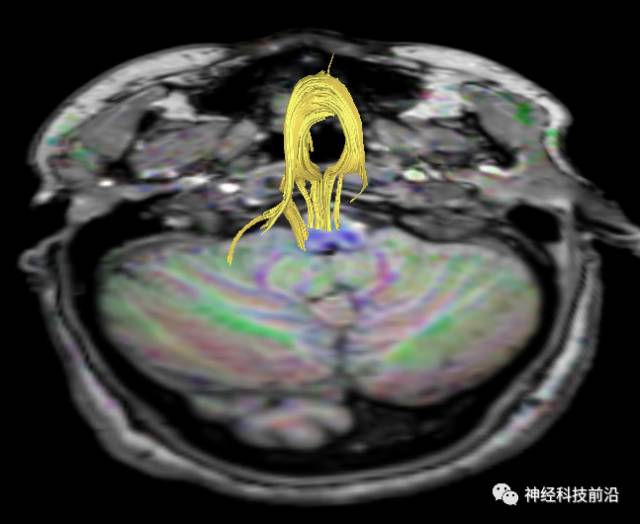

皮质脑桥束与脑干高信号(黄色)纤维束

脑干内高信号为一近环形纤维束,其作用尚待研究。